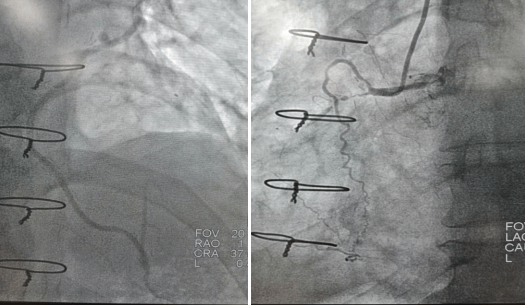

2022年9月16日行冠脈造影術(shù),造影結(jié)果示:左主干末端99%狹窄,LAD近段100%閉塞,LCX開口及近段95%狹窄,乳內(nèi)動脈-左前降支血管通暢,RCA近段100%閉塞,大隱靜脈橋血管未見,考慮閉塞。

心血管病院吳棟梁院長、CCU李新國副主任、心血管內(nèi)科二病區(qū)趙娟副主任、王端樂主治醫(yī)師、宋睿主治醫(yī)師介入團(tuán)隊造影后認(rèn)真研究患者的病情和影像資料,決定開通閉塞長達(dá)11年的右冠狀動脈,精確選擇器械,選擇同軸性及支撐力均好的指引導(dǎo)管,術(shù)中選用微導(dǎo)管輔助,軟、硬導(dǎo)絲結(jié)合等技術(shù),聚精會神、揮汗如雨,終于歷經(jīng)3小時的努力,成功前向開通右冠狀動脈,精準(zhǔn)選擇由遠(yuǎn)及近“鋪設(shè)”通過性較好、長度合適的支架 。

(術(shù)前術(shù)后對比)

術(shù)后癥狀明顯改善,活動后無胸悶、胸痛,明顯提高患者生活質(zhì)量,提高患者生存率,使患者絕地逢生。